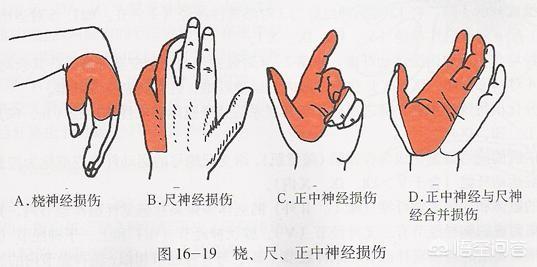

尺骨神経の損傷。同じ側の小指と薬指のしびれや痛み、一部の指の運動障害を引き起こすことがある。肘の後方にある尺骨神経の溝は、損傷や圧迫を受けやすい。

正中神経損傷: 前腕と上腕の正中神経は、外傷、腫瘍、圧迫などにより、手掌面、親指、人差し指、中指にしびれや痛みを生じる。手首は、手根管症候群と呼ばれる損傷や圧迫に対して最も脆弱であり、治療原則は以前と同じです。

橈骨神経の損傷橈骨神経は上腕側面の中央から下部にかけて傷害を受けやすく、親指と人差し指の甲のしびれや痛み、指と手首の下垂を伴う。

2.橈骨神経、正中神経、尺骨神経の損傷

上腕外側面の中央下部にある橈骨神経は、次のような影響を受ける。圧迫、外傷、腫瘍などにつながる可能性がある。親指と人差し指の裏側のしびれと痛み、指と手首の下垂。.正中神経が損傷すると、次のようなことが起こる。手のひら、親指、人差し指、中指のしびれと痛み。尺骨神経の損傷はその結果である。尺骨神経の損傷は、その後、次のような結果をもたらす。同側の小指と薬指にしびれと痛みがあり、一部の指の動きが悪くなる。

上記の神経損傷による指先のしびれ。ほとんどの場合、受傷後6カ月ほどで徐々に回復するしかし、腫瘍や完全骨折、重度の圧迫がある場合は、手術が必要になることが多い。

1.上肢の橈骨神経、正中神経、尺骨神経の損傷

この神経損傷は主に外傷、骨折、術後、腫瘍、頸椎圧迫などの要因で見られ、尺骨神経損傷は1~2本の指先のしびれが現れ、重症例では小指の爪の手の変形が現れ、正中神経損傷は上肢の感覚障害と筋機能障害の出現、親指と前腕の機能制限の出現につながり、橈骨神経損傷は指と手首の眼瞼下垂だけでなく、親指と人差し指も現れます背側のしびれと感覚障害。